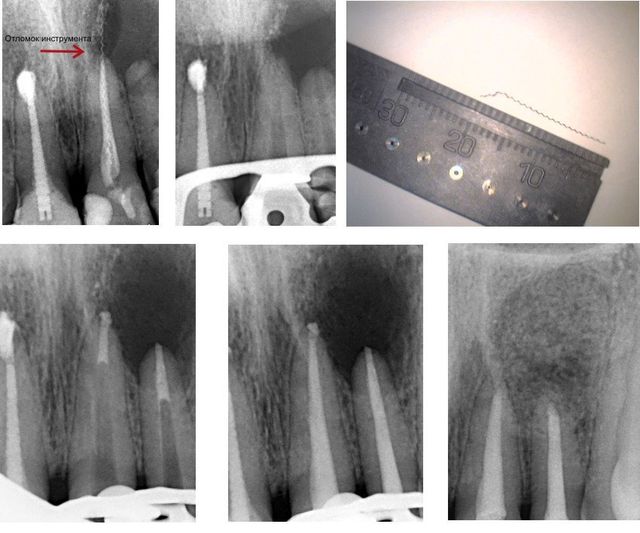

Одновизитная эндодонтия. Лечение кисты с помощью микроскопа за 1 посещение и удаление отломка инструмента.

Пациент испытывал боль в области передних верхних зубов и до того, как обратиться к нам, посетил несколько клиник, где ему констатировали большую кисту в области двух передних верхних зубов и рекомендовали эти два зуба удалить вместе с кистой. Мы диагностировали наличие отломка инструмента в канале зуба, уходящего за верхушку корня и большую кисту в области двух верхних передних зубов. С помощью микроскопа был извлечен отломок инструмента, как видно на снимках, отломок был 2 сантиметра в длинну и уходил в полость кисты. Верхушки каналов были закрыты MTA-ProRoot. В этот же день была проведена хирургическая манипуляция (в связи с огромным размером кисты: 13 х 15 мм) с удалением кисты и заполнением полости специальным биосвоместимым материалом — OsteoBiol. В результате пациенту были сохранены зубы, приведены в порядок каналы и полностью вылечена область, где была киста.

Врач терапевт: Свирко Елена Вячеславовна / Врач хирург: Рыков Дмитрий Валерианович